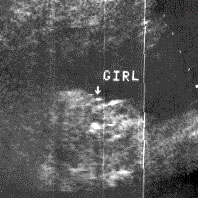

ثانيا : البنت

الاسبوع ال16